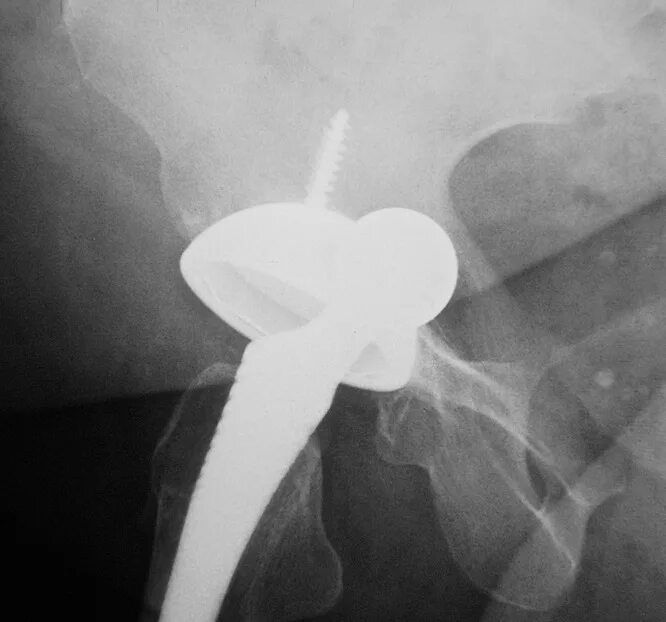

Расшатывание эндопротеза тазобедренного сустава